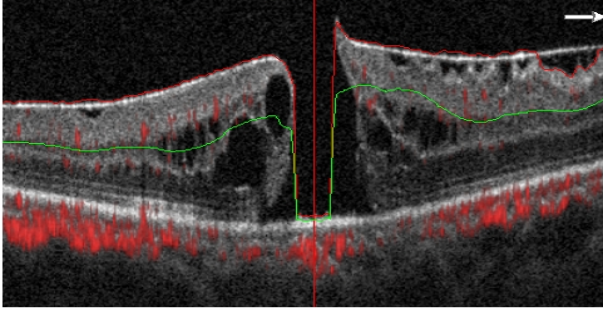

图2 特发性黄斑裂孔OCT图